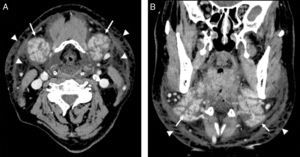

Presentación de los casosCaso 1Varón de 60 años de edad, con insuficiencia renal crónica y un valor de creatinina de 2mg/dl, que acudió a urgencias por un aumento brusco de los planos blandos de la región cervical, con sensación de disfagia, sin disnea ni estridor. En las 24 horas previas había sido sometido a una tomografía computarizada (TC) abdominopélvica, para la cual se le inyectaron 100ml de contraste yodado (Iohexol 300 mgI/ml, Omnipaque®, GE Healthcare Ireland, IDA Business Park Carrigtohill Co. Cork, Ireland). En la exploración física se objetivaron signos inflamatorios con eritema cutáneo. Ante la sospecha clínica inicial de un proceso infeccioso se decidió realizar una TC cervical con contraste intravenoso tras nefroprotección, para delimitar la formación de abscesos y su extensión ante un posible drenaje urgente. En la TC se identificó un aumento del tamaño de las glándulas submaxilares, con engrosamiento de los septos glandulares y moderados cambios inflamatorios asociados en la grasa circundante (fig. 1). No se visualizó causa obstructiva que justificara la inflamación ni tampoco abscesos cervicales. Se pautaron corticoides, con mejoría progresiva y resolución completa del cuadro clínico a las 72 horas.

Imagen axial (A) y coronal (B) de tomografía computarizada cervical con contraste intravenoso en la que se observa marcado aumento de ambas glándulas submaxilares (flechas), que se muestran hipercaptantes y con engrosamiento de los septos glandulares. Se asocia a moderados cambios inflamatorios en la grasa circundante y en el tejido celular subcutáneo (puntas de flecha). No se visualizan colecciones definidas en la región cervical.